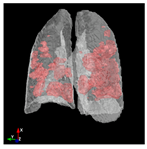

3.6. Post-Processing: 3D Projection

To generate a 3D projection from the 2D output, a post-processing step is required. This step involves aggregating the CT image slices and transforming them into a coherent 3D representation. In this process, the Mayavi [59] library in Python serves as a valuable tool for facilitating the conversion of the 2D model output into a 3D representation.

The process begins by obtaining segmentation masks for each individual slice of the CT-scan. These masks provide information about the different regions within the lung. Next, the segmented slices are merged to create a unified representation. This merging process involves swapping the axes of the segmented data, ensuring that the resulting 3D projection can be visualized as a cohesive volume.

The utilization of the Mayavi library streamlines the transition of the 2D model output to a 3D representation. This library offers robust functionality for transforming and displaying the segmented data in a three-dimensional space. By employing Mayavi, the proposed approach enhances diagnostic capabilities, providing clinicians with a comprehensive 3D visualization of lung structures and infection areas.

In Table 6, a comparison of the ground truth and prediction results of each model is presented in 2D, along with the 3D projection of each model. The visual analysis of the predictions provides additional insights into the performance of each model. The visualizations demonstrate that Attention UNet captures the intricate details of the lung construction more accurately, resulting in more precise segmentation of the infected areas compared to other models.